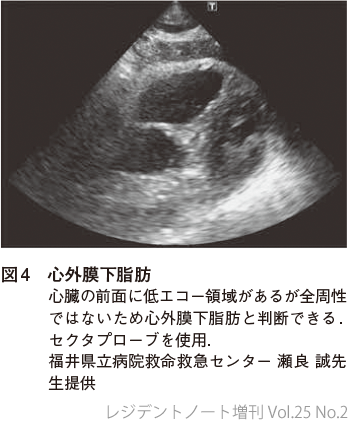

心室壁よりも外側に液体貯留があるかどうか確認する(図2,3).

3うまく描出できないときは

胃,腸管のガスなどで心窩部像の描出が難しい場合は,心尖部,傍胸骨,肋間から観察する.コンベックスプローブの代わりにセクタプローブを用いてもよい.